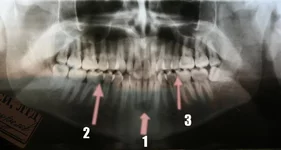

-Перелом угла нижней челюсти справа.

-Есть еще место, которое требует уточнения, это затемнение в области верхушек нижних резцов. Возможно неполный вывих зубов, возможно, поэтому это место было более болезненным.

-Еще на снимке видна кариозная полость в первом моляре на нижней челюсти справа («шестерка»).

-На приеме у стоматолога надо проверить такой же зуб слева.

-Про зуб мудрости на нижней челюсти слева Вам не могли не сказать, хирурги любят об этом говорить.

1. затемнение в области верхушек корней нижних резцов

2. кариозная полость большого размера

3. кариозная полость ?